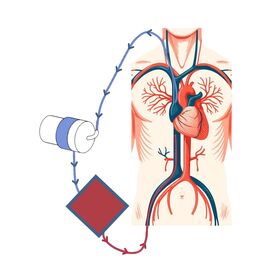

Kórónuveirusjúkdómurinn (COVID-19) orsakast af SARS-CoV-2 veirunni sem leggst aðallega á öndunarfæri þar sem hún veldur oftast vægum sjúkdómi. Í sumum tilvikum nær veiran þó að valda alvarlegri lungnabólgu sem getur leitt til bráðs andnauðarheilkennis (acute respiratory distress syndrome, ARDS).1,2 Sjúklingarnir eru þá lagðir inn á gjörgæslu þar sem auk meðferðar með veirulyfjum, barksterum og líftæknilyfjum, er hægt að tengja þá við öndunarvél. Sjúklingunum eru þá einnig stundum snúið á grúfu og/eða gefin vöðvaslakandi lyf sem hvort tveggja getur bætt loftskipti.1 Dugi slík meðferð ekki til að leiðrétta öndunarbilunina, er síðasta meðferðarúrræðið að grípa til lungnadælu (VV-ECMO).3 Um er að ræða loftskipti utan líkamans þar sem grófur æðaleggur er þræddur upp í gegnum nárabláæð (femoral vein) í neðanverða neðri holæð. Annar æðaleggur er síðan þræddur niður hóstarbláæð (internal jugular vein) um efri holæð að hægri gátt hjartans (mynd1).

Oftast er blóðinu veitt um neðri holæðarlegginn til gervilungans þar sem það er mettað súrefni og koltvísýringur hreinsaður úr því. Blóðinu er síðan dælt um hóstarbláæð og efri holæð inn í hægri gátt hjartans.4 Einnig má snúa blóðflæðinu við, það er draga blóð úr hægri gátt og dæla því síðan inn um nárabláæð. Þannig er hægt að ,,hvíla lungun“ og gefa þeim tíma og tækifæri til að ná sér, um leið og súrefnismettun er tryggð.5 Í undantekningartilfellum geta sjúklingar fengið lungnadælumeðferð sem tímabundið úrræði í bið eftir lungnaígræðslu. Lungnadælumeðferð er þó ekki hættulaus og ýmsir fylgikvillar geta tengst henni, ekki síst blóðsegamyndun og sýkingar. Þessum sjúklingum eru því gefin sýklalyf í æð og blóðþynnandi meðferð með heparíni til að minnka blóðsegahættu, sem aftur á móti getur aukið hættu á blæðingum.4